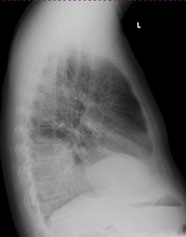

Radiologie Quiz 47

Ein 68-jähriger Patient mit chronischer Niereninsuffizienz und hypertensiver Herzerkrankung klagt akutell über zunehmende Dyspnoe. Sie veranlassen ein Thoraxröntgen.